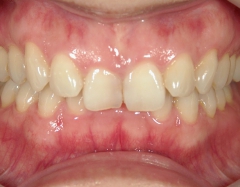

矯正歯科 治療前

36歳女性 磐田市

在住

治療期間2年6

ヶ月